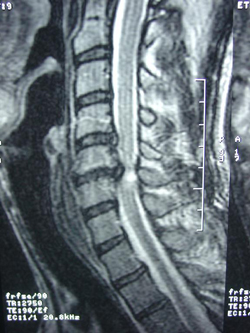

xray of cervical spine myelopathy